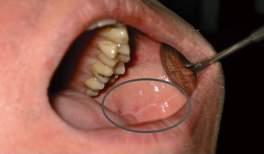

Rycina 5.2. Badanie mięśnia skrzydłowego bocznego

Następnie przystępujemy do badania błony śluzowej policzka i języka, szukając linea alba (patrz ryc. 5.5). Biaława linia anemizacji na błonie śluzowej policzków powstaje na skutek wtłaczania błony śluzowej pomiędzy zaciśnięte zęby przez kurczące się mięśnie żwacze, zaś na języku przez kurczący się na boki i do przodu język.

Rycina 5.5. Linea alba − anemizacja błony śluzowej policzków na wysokości powierzchni żujących zębów bocznych. Powstaje w wyniku wtłoczenia przez napięte mięśnie żwacze błony śluzowej policzka pomiędzy zaciśnięte zęby